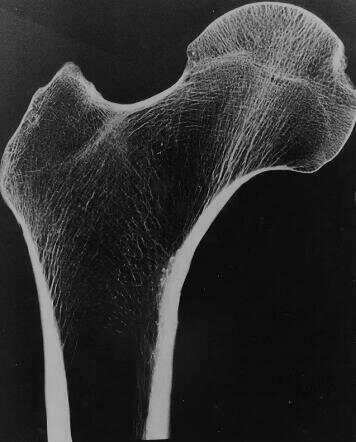

人體骨骼通過小梁的海綿狀結(jié)構(gòu)獲得耐用性,這種海綿狀結(jié)構(gòu)是由相互連接的垂直柱狀支撐和水平桿狀支撐作為柱和梁組成的網(wǎng)絡(luò)。小梁越密集骨骼在日常活動(dòng)中就越有彈性,但是疾病和年齡會(huì)影響這種密度。

人類股骨的圖像顯示出相互連接的白線,這些線構(gòu)成了小梁結(jié)構(gòu)。

來源:普渡大學(xué)